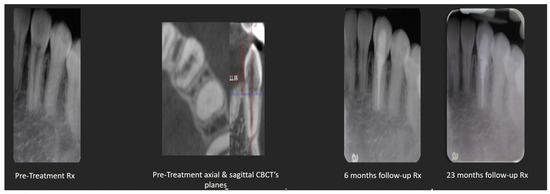

2.2. Cracked Tooth